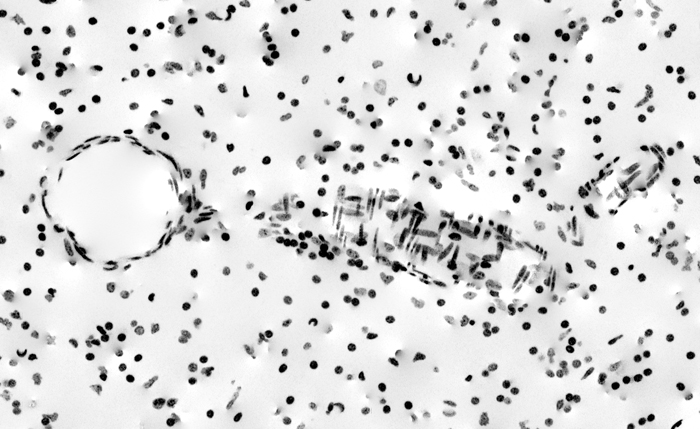

Complicated Retinal Detatchment

This set of images (click the image above to enlarge) are optical coherence tomography (OCT) images of retained perfluoro-octane(PFO) droplets after repair of a complicated retinal detachment. PFO is a good surgical tool to help reattach the retina as they force sub retinal fluid out of any retinal tears and helps adhere the retina …